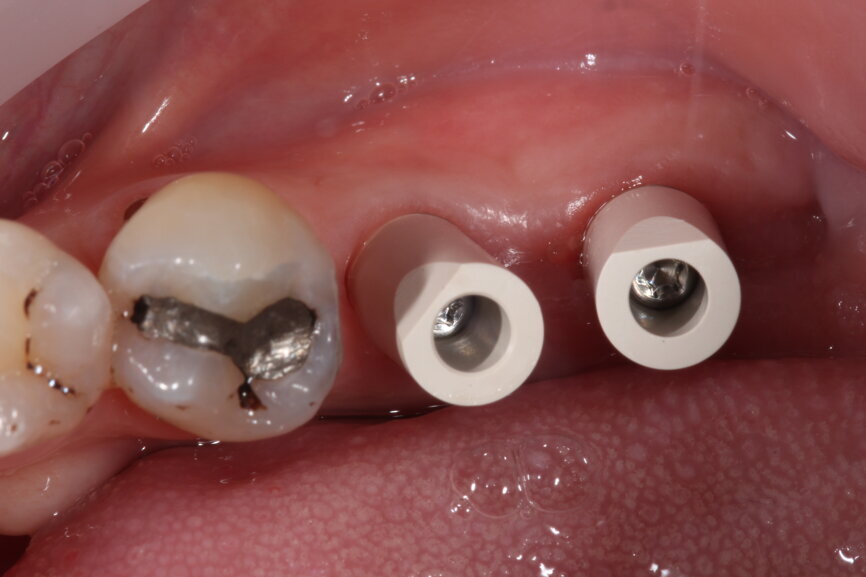

Fig. 9: Surgical placement of LL67 implants.

Fig. 11: Tissue level implants.

Once the implants are placed in situ and fully integrated, we then have a choice of conventional wet impression techniques versus digital intra-oral scanning. For the majority of cases, intra-oral scanning is extremely predictable and reliable—more so than conventional techniques—with milled (and lately printed) models having excellent properties and less accumulation of processing errors. However, deeply placed implants relative to adjacent teeth with deep contact points are very difficult to scan and pick up. Straumann tissue level implants offer a very straightforward restorative platform to scan from.